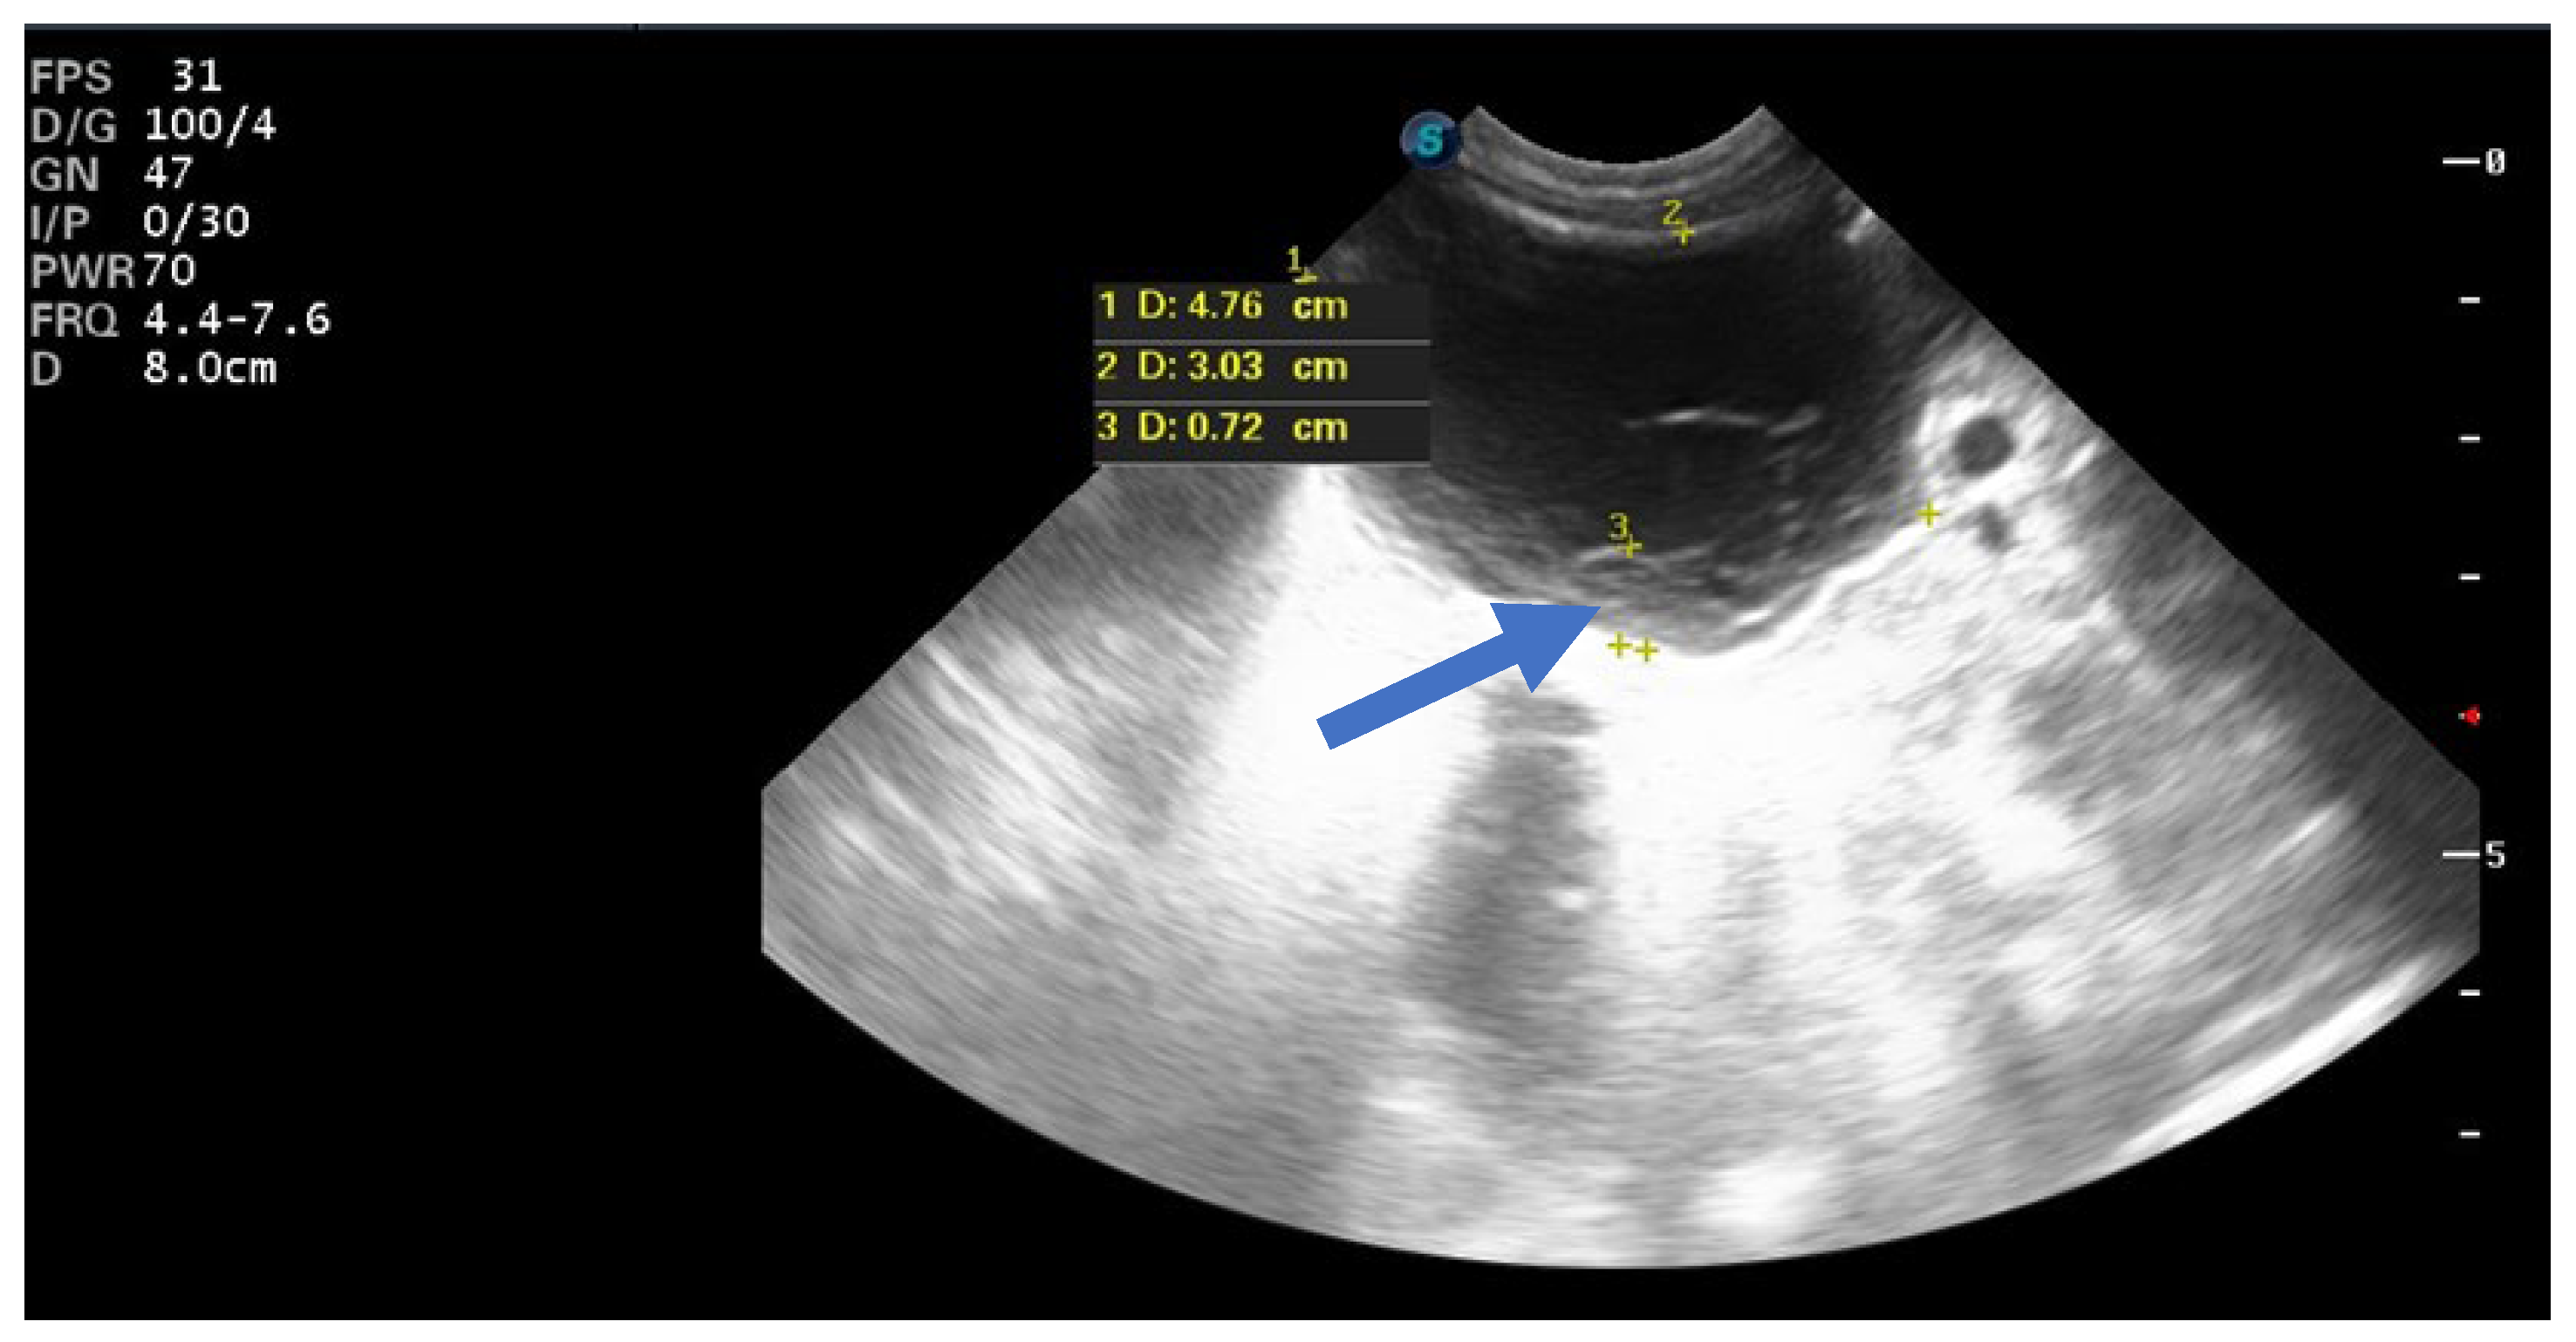

In 25% of cases, the cyst had the appearance of a complex cyst. On ultrasound, we observed the presence of internal echoes, indicating the presence of intracystic hemorrhage with round or crescent-shaped echogenic areas due to retraction of intracystic clots. We also noted fluid levels (liquid level) and sometimes the presence of microcalcifications at the level of the cyst walls (Figure 4).

Figure 4.

Ultrasound axial view. Right ovarian complex cyst in the 32nd week of pregnancy with a size of 6/4 cm and an echolucent stratification (arrow) corresponding to a hemorrhagic ovarian cyst.